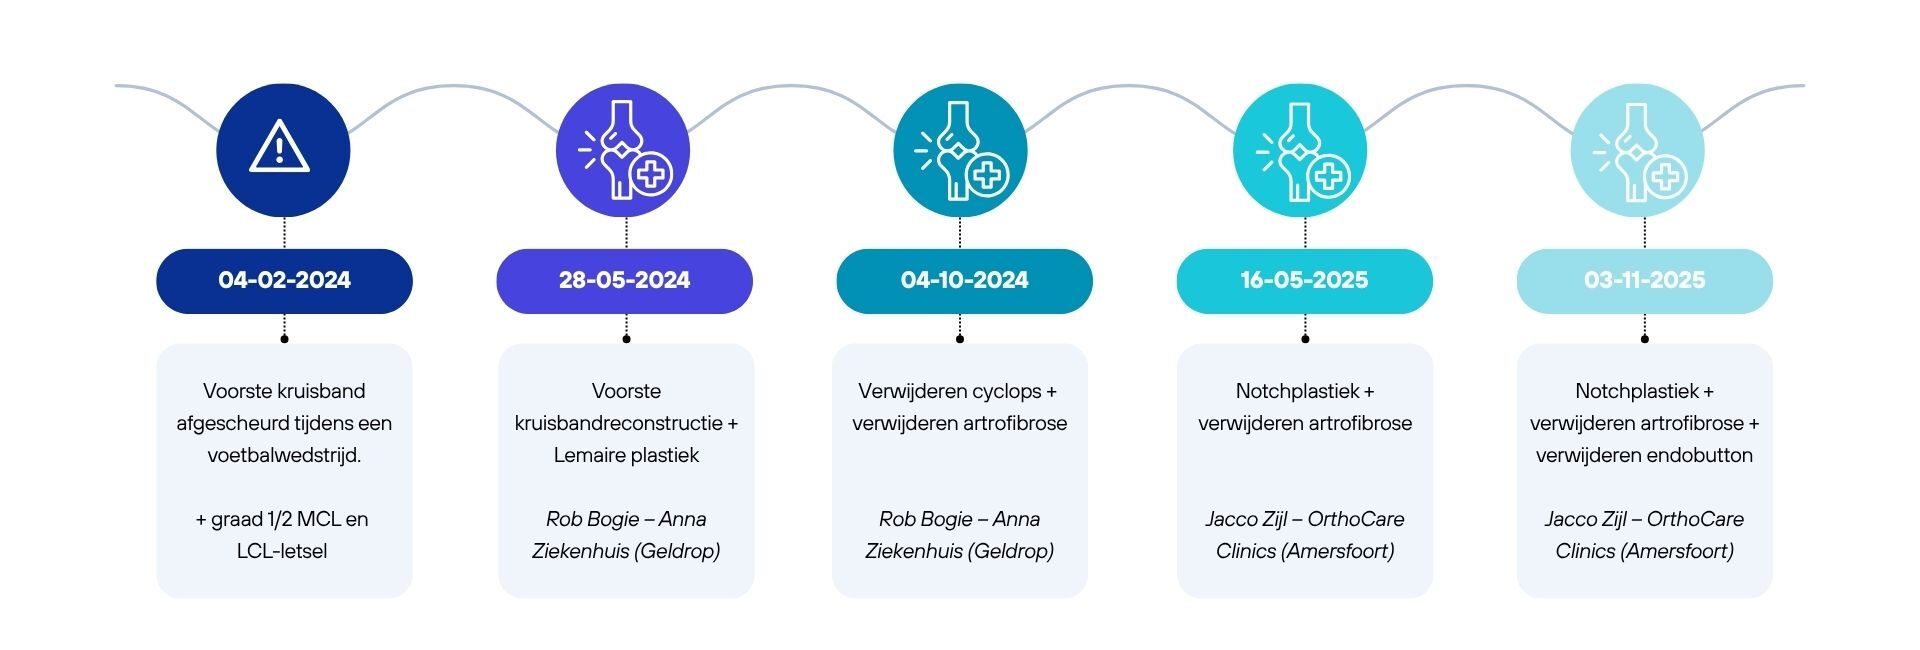

Voorste kruisband traject in vogelvlucht